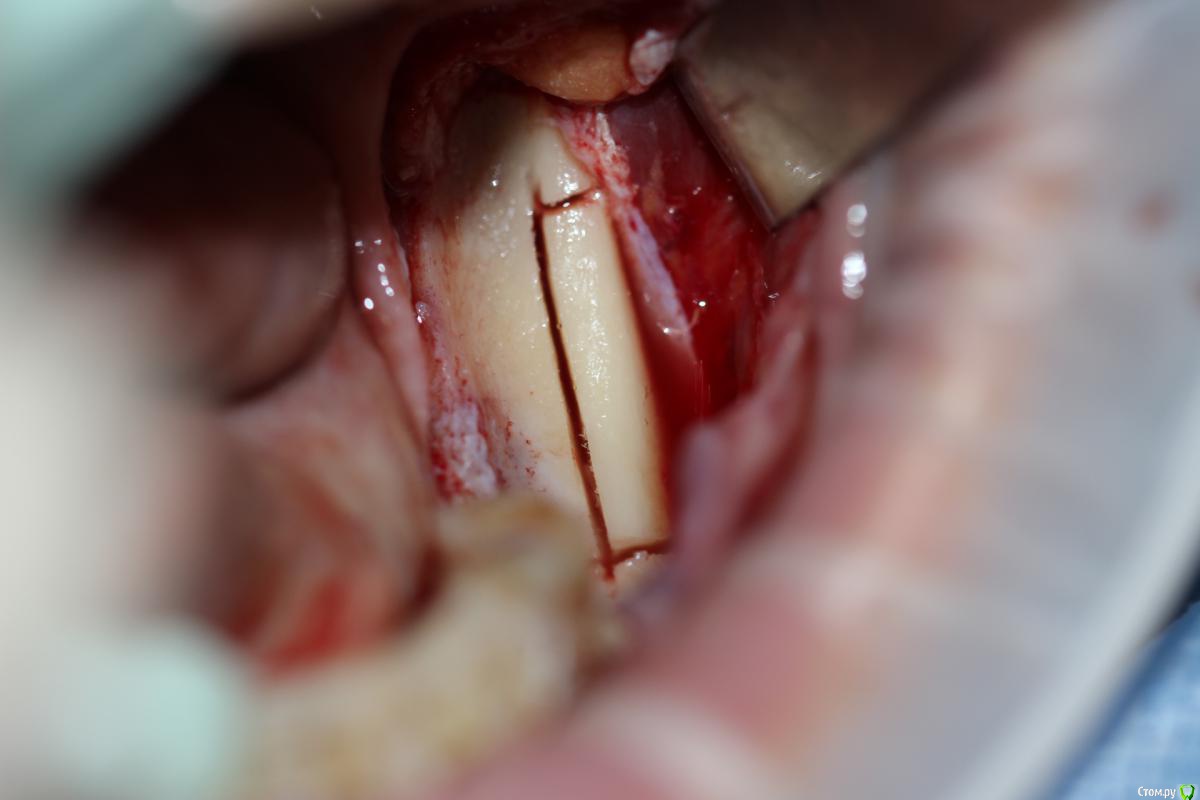

АнтонТЛТ Опубликовано 22 декабря, 2014 Поделиться Опубликовано 22 декабря, 2014 Название темы не соответствует выложенному кейсу. Тут не блоки, а ламинаты. И в классике нет графта, чистый ауто Ссылка на комментарий

Bier Опубликовано 22 декабря, 2014 Поделиться Опубликовано 22 декабря, 2014 в 3м, где вертикалили. Ссылка на комментарий